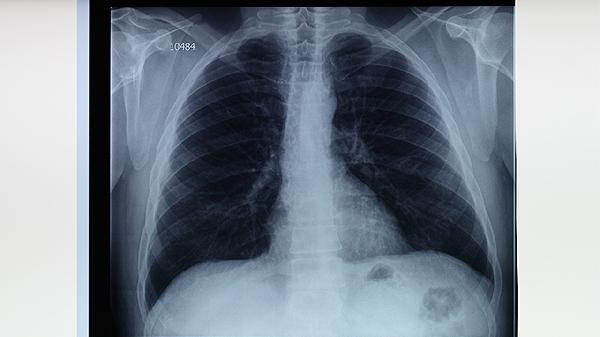

肺结核性结膜炎患者除规范用药外,应保持饮食均衡,避免辛辣刺激食物加重眼部不适。每日保证2000毫升饮水促进药物代谢,室内活动时佩戴防尘眼镜减少刺激。建议分餐制避免交叉感染,餐具需定期煮沸消毒。保证充足睡眠有助于免疫力恢复,康复期间避免过度用眼,定期复查胸片和眼部情况。出现视力模糊、眼痛加剧等症状需立即复诊。